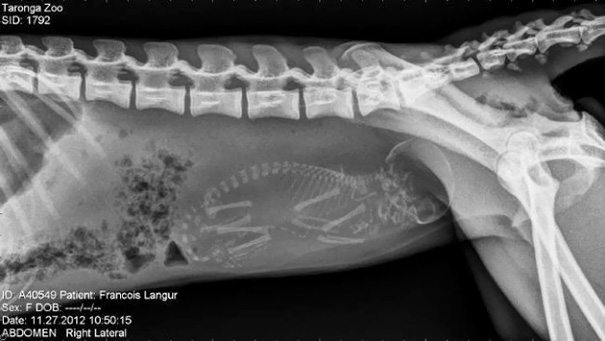

Francois Langur Monkey – doesn’t it look so much like a human?

3-pregnant-animal-x-rays-that-are-both-awesome-and-scary